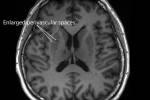

وأفاد "معهد وورشيستر بوليتكنيك"Worcester Polytechnic Institute في ولاية ماساتشوستس الخميس بأن تحليل أكثر من 800 صورة مسح دماغي مكن الذكاء الاصطناعي من تحديد التغيرات التشريحية في الدماغ التي تشير إلى بداية أكثر أنواع الخرف شيوعاً.

وجمعت صور الرنين المغناطيسي من 344 شخصاً تراوح أعمارهم ما بين 69 و84 سنة، وشملت 281 صورة لأدمغة ذات وظائف عقلية طبيعية، و332 صورة لحالات تعاني ضعفاً إدراكياً خفيفاً، و202 صورة لأشخاص مصابين بمرض ألزهايمر.

وشملت التحليلات 95 منطقة من أصل نحو 200 منطقة متميزة في الدماغ، إذ استخدمت خوارزمية للذكاء الاصطناعي للتنبؤ بالحالة الصحية للمرضى.

وأظهر التحليل أن أحد أبرز المؤشرات التنبئية للإصابة بمرض ألزهايمر هو ضمور حجم الدماغ، وهو ما يحدث عندما تتوقف خلايا الدماغ عن العمل في مناطق مثل الحصين المسؤول عن تكوين الذاكرة، واللوزة الدماغية المعنية بمعالجة الخوف، والقشرة الأنفية الداخلية المرتبطة بالإحساس بالزمن.

وانطبق ذلك على مختلف الفئات العمرية وكلا الجنسين، إذ أظهر كل من الرجال والنساء الذين تراوح أعمارهم ما بين 69 و76 سنة تراجعاً في حجم الدماغ في الجزء الأيمن من الحصين، مما يشير إلى أهمية هذه المنطقة في التشخيص المبكر، وفق الباحثين.